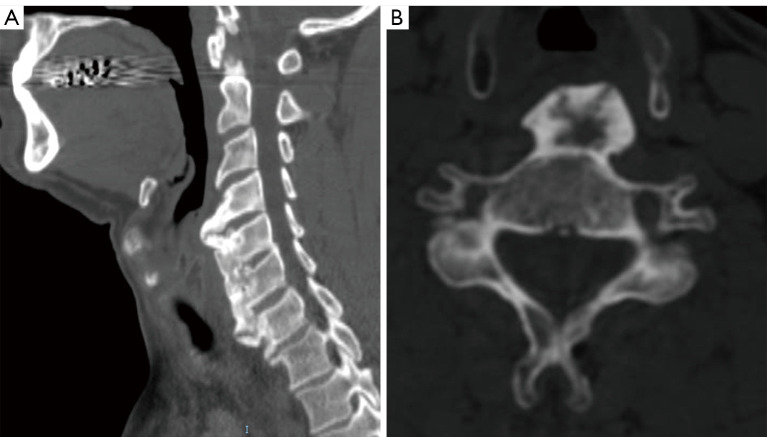

Case description: We report the case of a 51-year-old man, with no specific past medical history, who has been complaining of a 3-months pain in the left side of the tongue base with sensation of a lump in the throat and dysphagia. Computed tomography scan confirmed DISH between C4 and C7. Barium swallow fluoroscopy demonstrated indentation of the esophagus only at the level of C4-C5, which guided the surgical management that focused on resecting only the major osteophytes at the level of C4-C5, avoiding extensive approach with its subsequent possible complications, and enabling satisfactory clinical and radiological outcomes.

Conclusions: The current case thoroughly illustrated the diagnosis and surgical management in the presence of dysphagia from DISH. Through an anterior pre-vascular approach complete resection of the major osteophytes could be done. Barium swallow fluoroscopy showed very high interest in dynamically demonstrating the main level causing the dysphagia symptoms and also confirming satisfactory esophagus decompression and release after surgery.